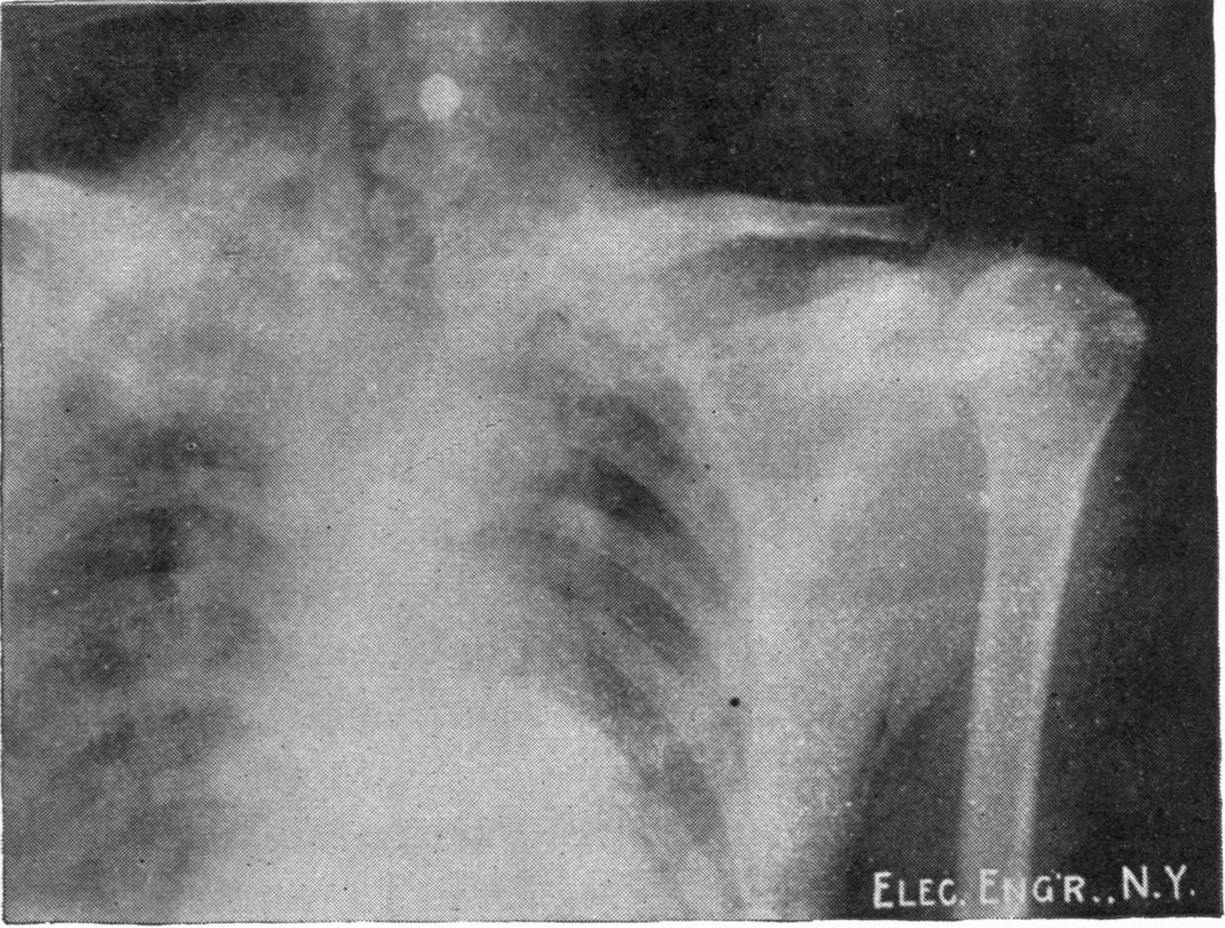

Fig. 2.—Broken Arm, Overlapping.

(Due to defective setting.)

Fig. 3.—Ribs.

Fig. 4.—Knee, Knickerbocker Buttons, Bullet in Femur.

FROM SCIAGRAPHS BY PROF. DAYTON C. MILLER. § 204.